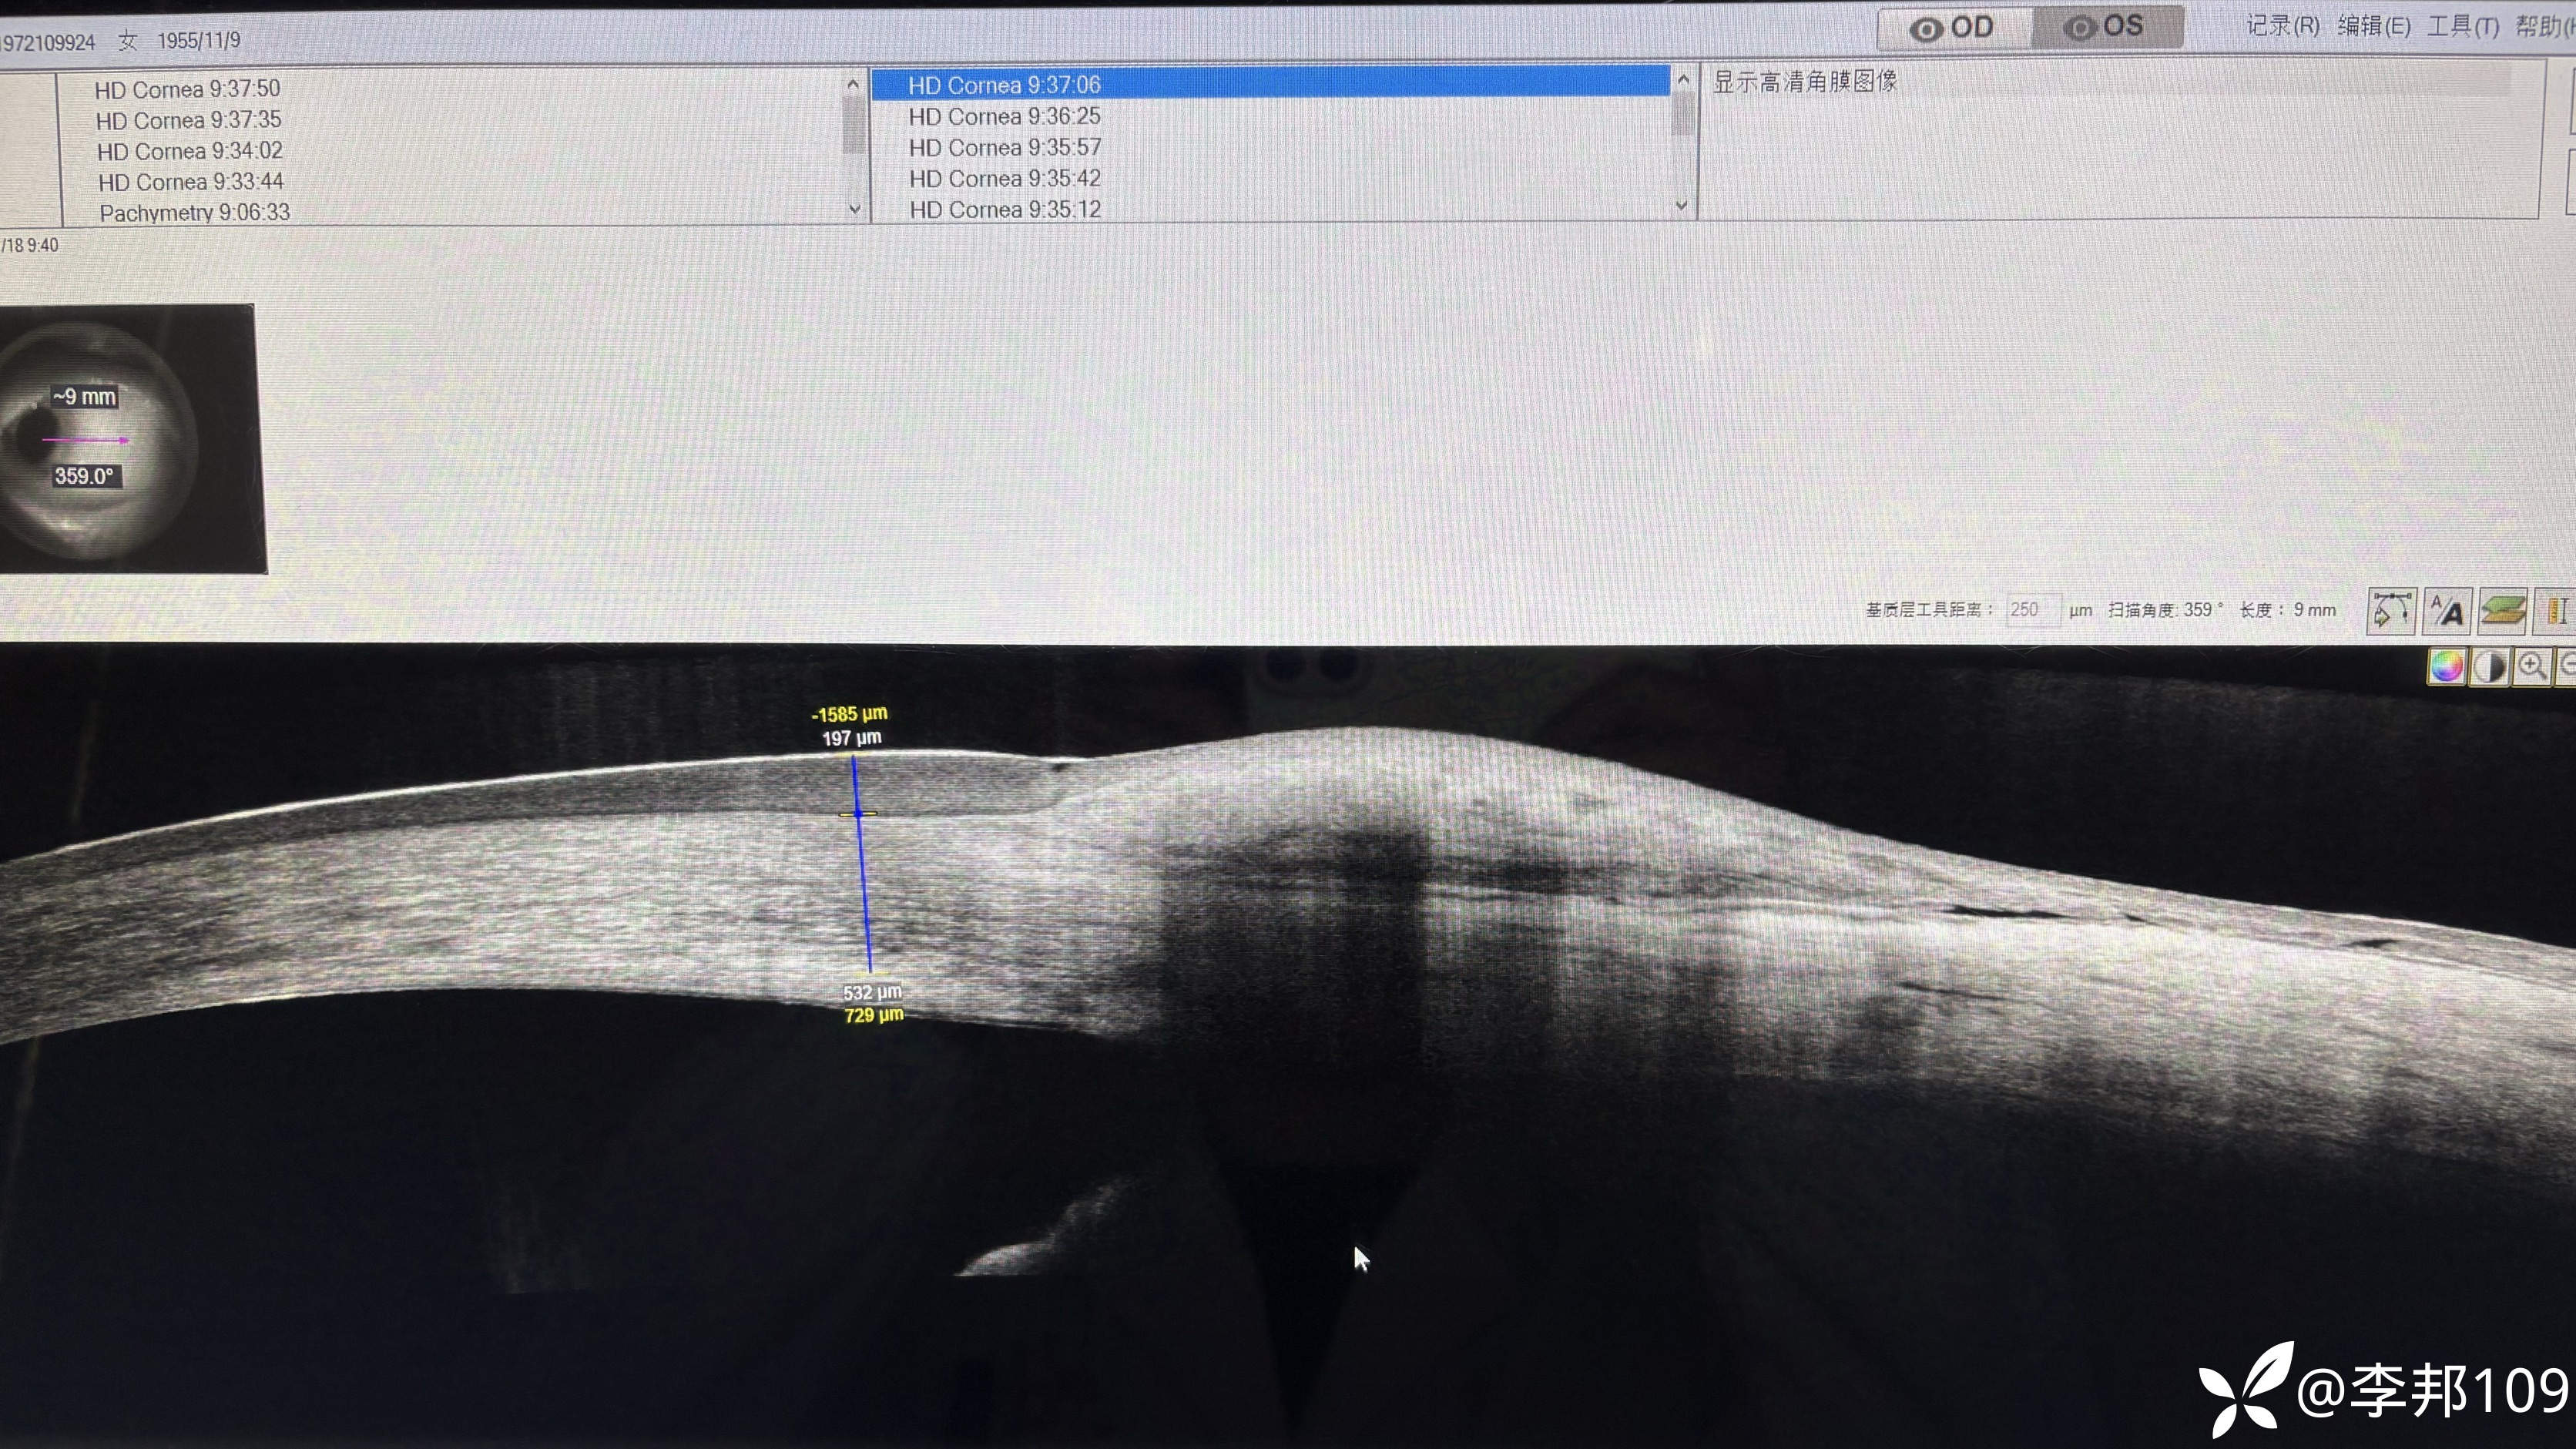

以为是睑裂班附近的角膜上皮是增厚的;于是做了一下右眼作对比,右眼不增厚;

双眼角膜上皮厚度不一样,干脆又做了一个角膜上皮厚度检查;

左侧角膜上皮厚度明显增厚;

左眼上下方的角膜上皮厚度有些地方正常;主要是鼻侧和颞侧为主;

难道是睑裂区的“胬肉 ”和“”睑裂斑“” 引起的鼻 颞侧的角膜上皮增厚? 或者还有其他元婴引起的散光问题?